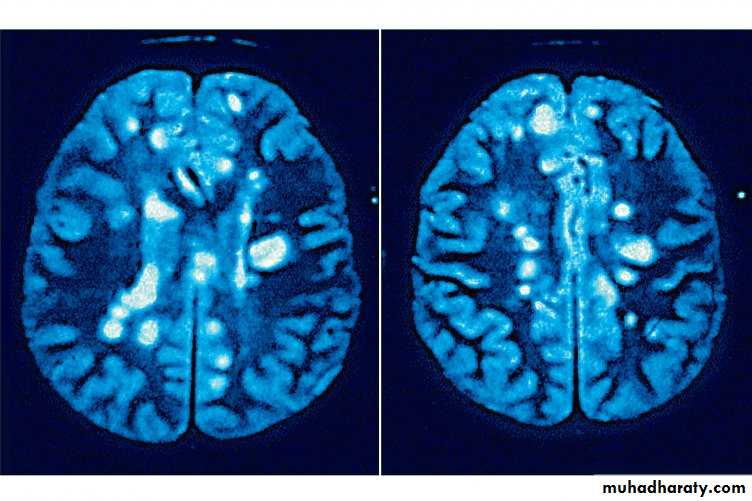

• - MRI:• characteristic abnormalities (plaques) are found in >95% of patients, although more than 90% of the lesions visualized by MRI are asymptomatic

• Plaques are frequently oriented perpendicular to the ventricular surface,

• Plaques are multi-focal within the brain, brain-stem, and spinal cord

• Plaque larger than 6 mm particularly helpful

• Recent plaque show Gd enhancement persists for approximately 1 month

• Old MS plaque remains visible indefinitely as a focal area of hyperintensity (a lesion) on spin-echo (T2-weighted) and protondensity images

Brain MRI films of M.S